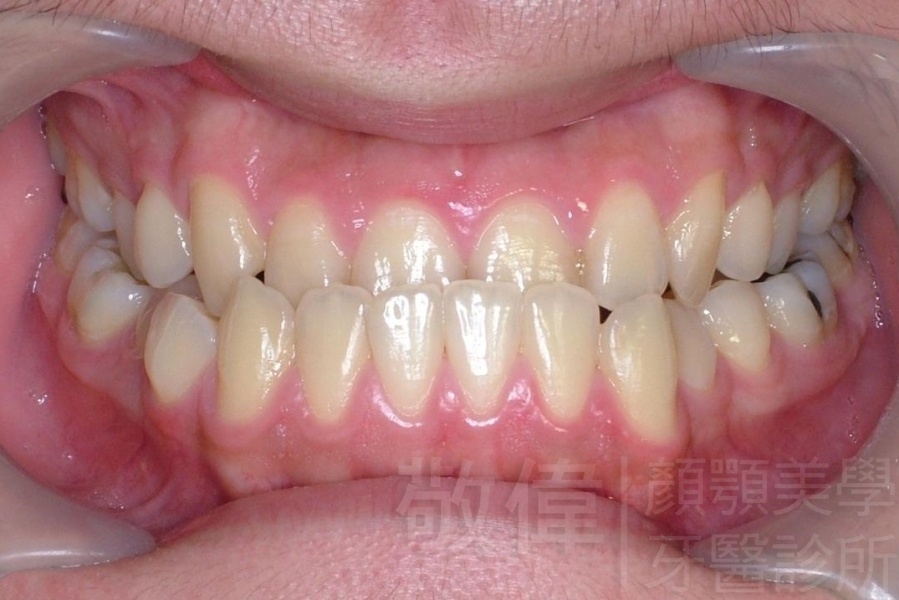

齒顏矯正/上下暴牙嘴唇不容易合起來

矯正前-右   矯正前-正   矯正前-左

矯正後-右   矯正後-正   矯正後-左

<個案說明>

上下暴牙嘴唇不容易合起來,經矯正完成後,嘴唇很容易合起來。在學生時期的時候的他,舉止之間充滿著有自信,當時還參加了舞蹈社團,充滿了多采多姿的生活。